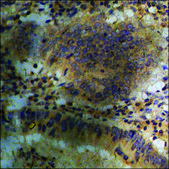

technique(s)

ELISA: 1:5000, immunohistochemistry: 1:50-1:100, western blot: 1:500-1:1000